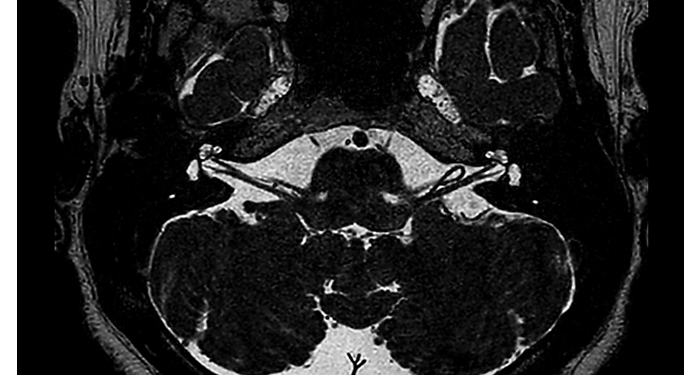

Hospital Eramse, Bélgica

Imágenes de la IRM de campos oscuros de un paciente con VIH con vasculitis cerebral

Las imágenes de campos oscuros ayudaron a sugerir el diagnóstico y elegir el tratamiento.